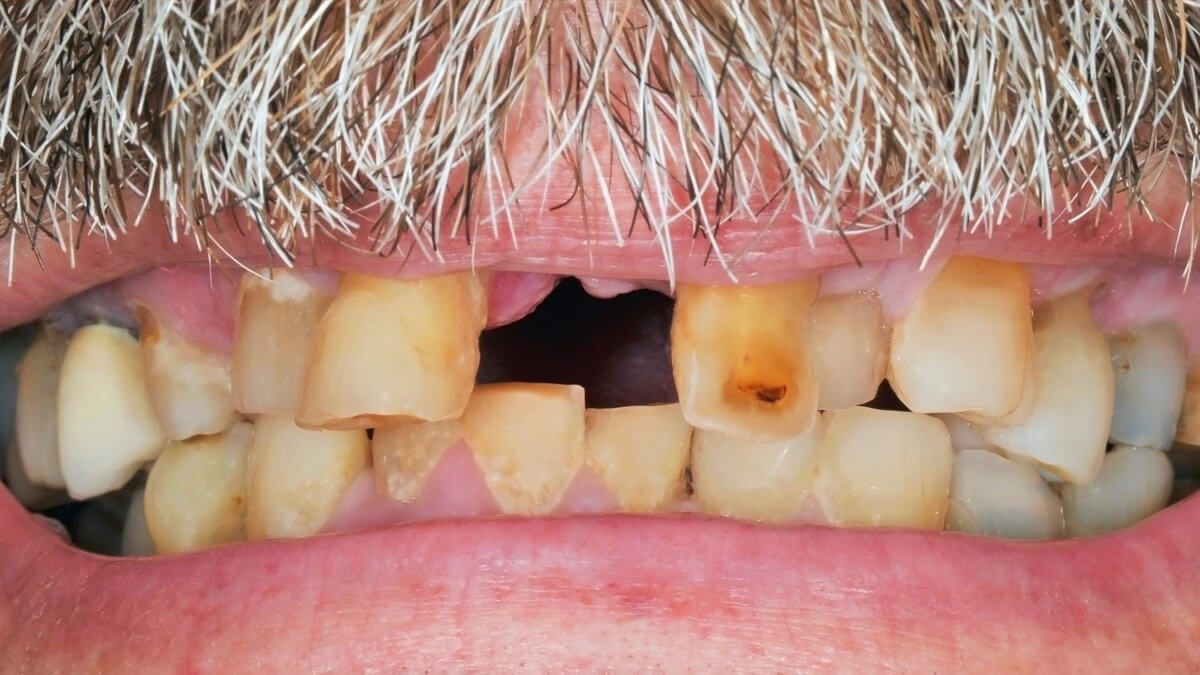

Fogaink külső felszínét szervezetünk legkeményebb anyaga, a zománc borítja. A zománc 98%-át szervetlen anyagok alkotják, amelyek savhatásra képesek kioldódni. Ez a magyarázata annak, hogy egy ilyen kemény anyag képes meggyengülni, sőt üreg képződhet pusztán baktériumok és szénhidrát hatására. Abban az esetben, ha a kórokozók átjutottak a zománc rétegen, a fogszuvasodás terjedése felgyorsulhat , ilyenkor általában már panaszos a fog, hidegre, édesre intenzívebben reagál.